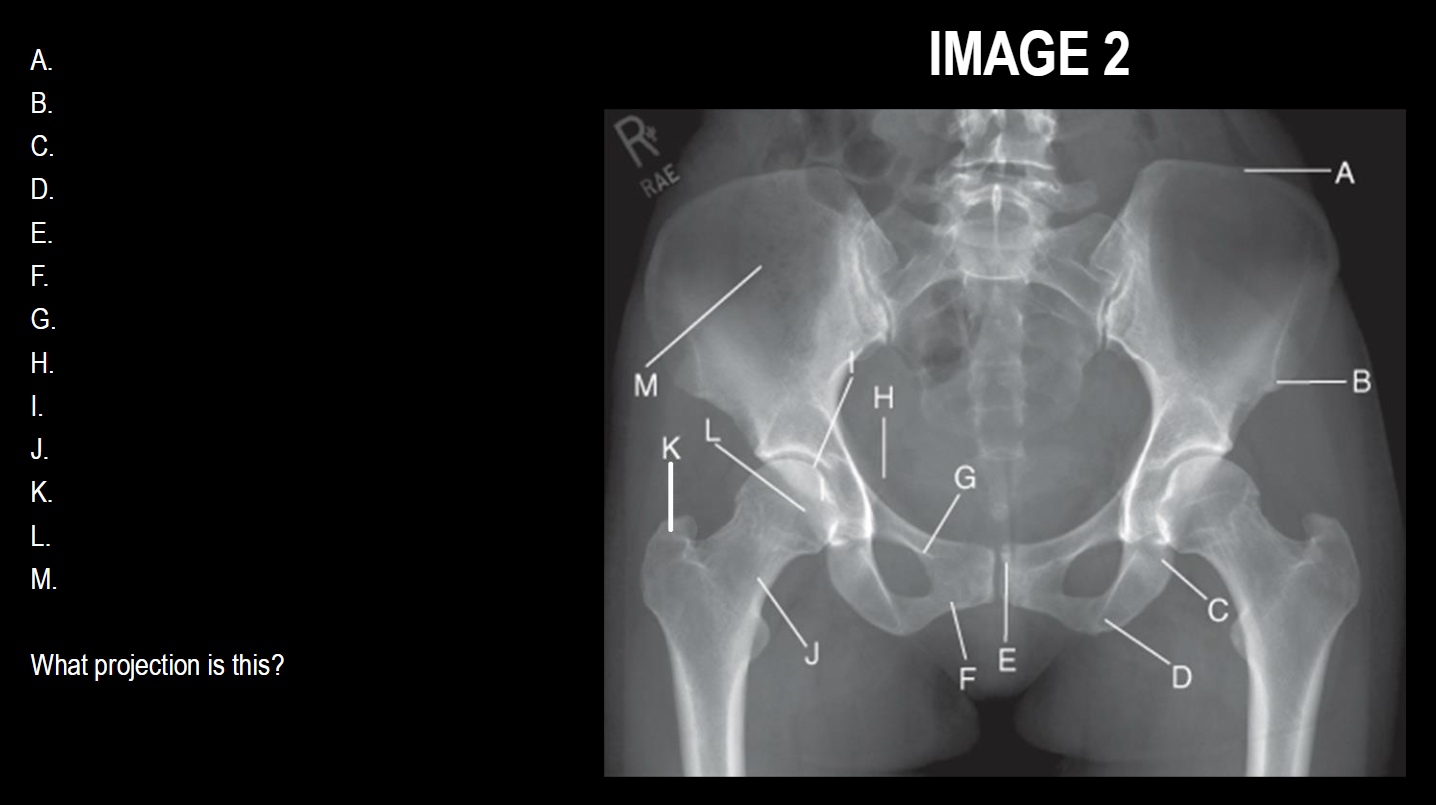

A

left iliac crest

B

ASIS

C

ischial body

D

ischial tuberosity

E

pubic symphysis

F

inferior ramus of pubis

G

superior ramus of pubis

H

ischial spine

I

acetabulum

J

femoral neck

K

greater trochanter

L

femoral head

M

ala/wing of ilum

What projection is this

AP Pelvis